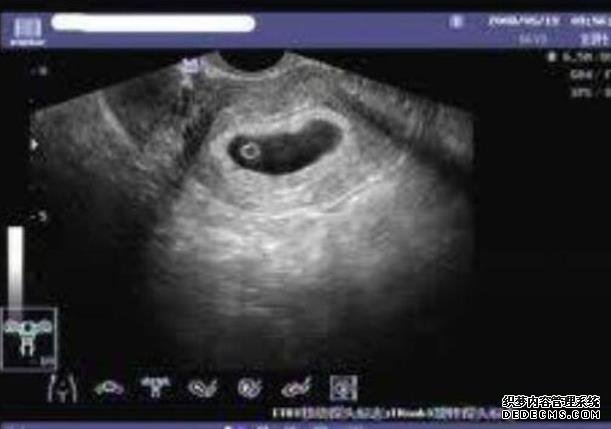

无锡借卵子生子的过程 2无锡101医院做试管成功率能达到多少? ‘代孕9周怀男孩彩超图’